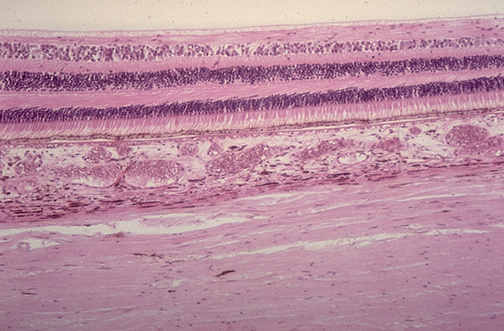

| Here is the normal adult retina of the eye at high power. Starting anteriorly can be seen the inner limiting membrane, the layer of nerve fibers, the ganglion cell layer, the inner plexiform layer, the inner nuclear layer, the outer plexiform layer, the outer nuclear layer, the outer limiting membrane, the layer of rods and cones, and the layer of pigment epithelium. Next comes the choroid, consisting of the choriocapillaris, the vessel layer, and the epichoroid. Finally, the sclera forms the capsule of the globe. |